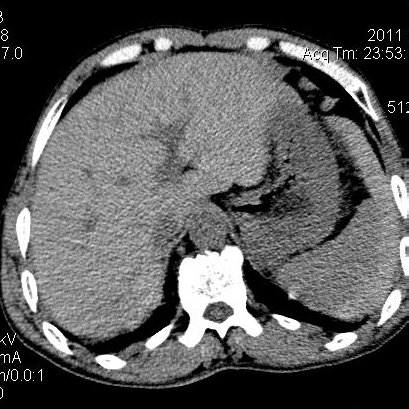

肝左叶发育异常

男性,55岁,骑摩托车摔倒后入院,自述右上腹疼痛

[backcolor=#FF0000]第一次诊断的时候也是这么肯定,可是床旁超声检查并没有发现明显异常,而且患者的一般症状都良好。还好临床只是保守治疗,没有立即手术,第二次复查的时候没有一点变化,又做了MRI检查,没有血肿,

这是一例肝左叶发育异常的,很个性吧~[/backcolor]